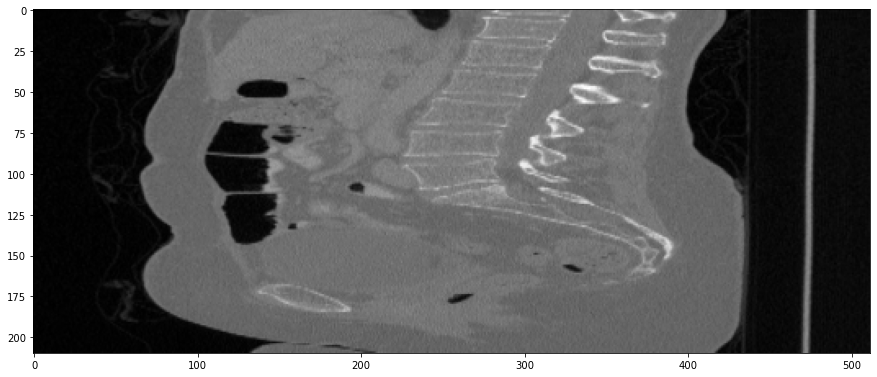

Figure 3: Coronal-plane thick-slice image quality comparison across four simulation methods.

Refer to caption

(a) True Thick-slice image

(b) Simple Averaging

RMSE: 0.0357, PSNR: 34.9781

(c) Gaussian Averaging

RMSE: 0.0454, PSNR: 32.8866

(d) Direct Downsampling

RMSE: 0.0486, PSNR: 32.2861

(e) Proposed Simulation

RMSE: 0.0070, PSNR: 49.1774

Figure 4: Sagittal-plane thick-slice image quality comparison across four simulation methods.